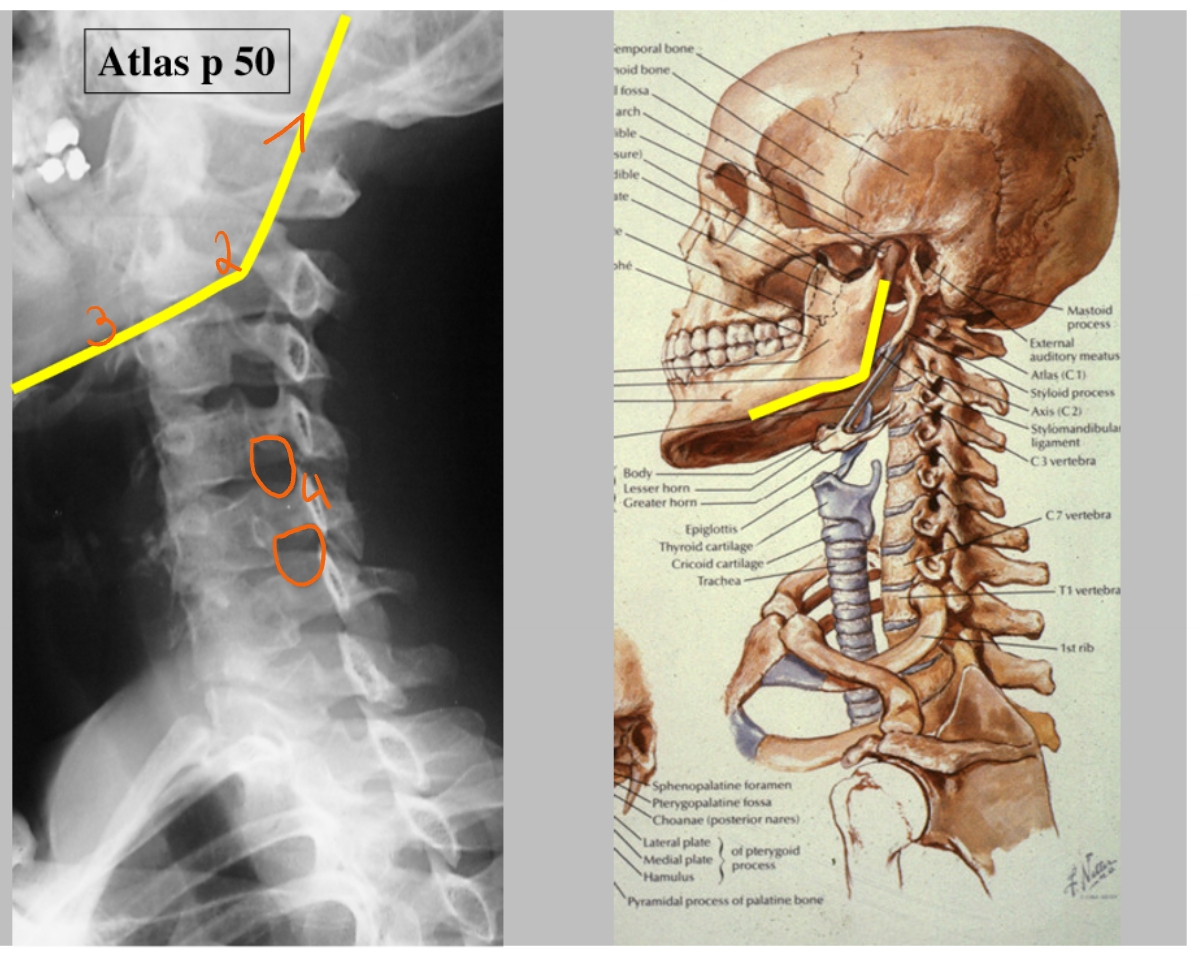

arcus anterior C1

→ articulatio atlanto-axialisch-mediana = gewricht (daarrond roteren we ons hoofd)

dens axis

arcus posterior C1

processus spinosus C2

corpus C4

corpus C6

processus spinosus C7

processus articularis superior C6 & processus articularis inferior C6 → facetgewricht

processus spinosus C6

ramus mandibulae

angulus mandibulae

corpus mandibulae

formamina intervertebrale

hier komen de spinale zenuwen uit

(linker beeld → linkerkaak)